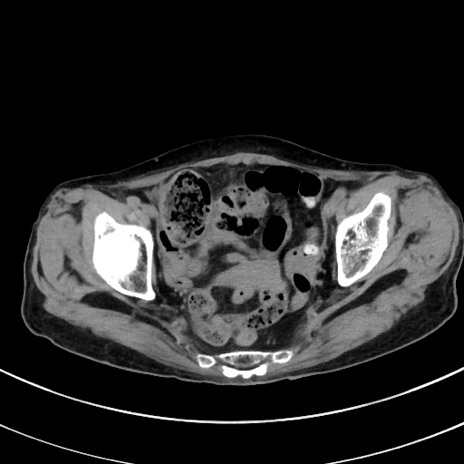

症例33(横断像)

冠状断像